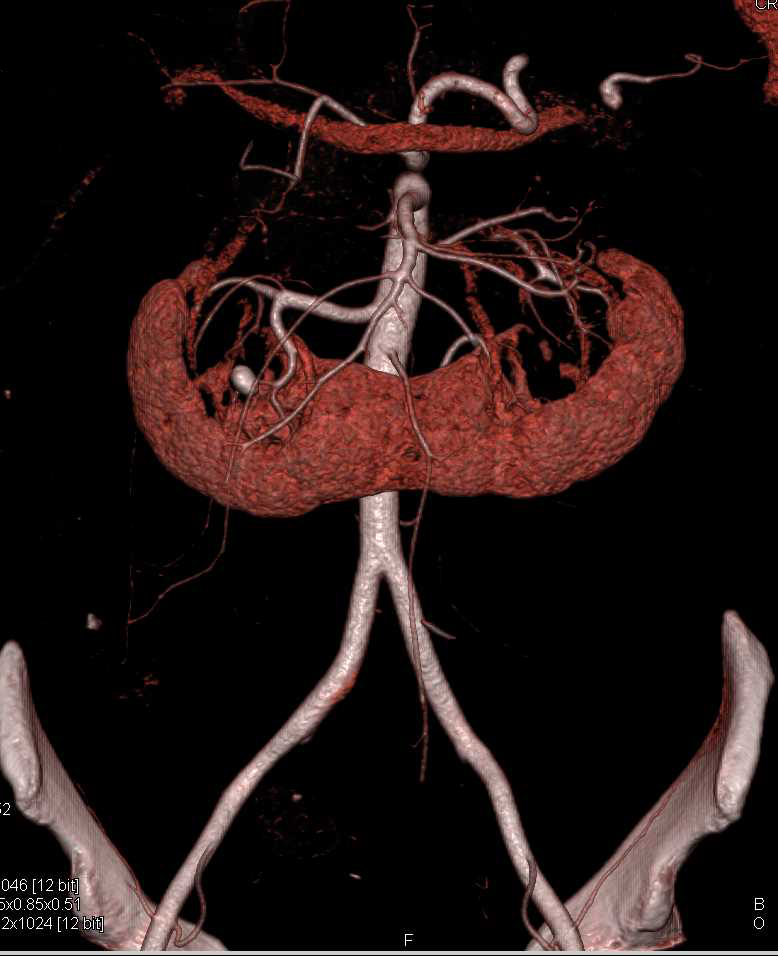

From www.ctisus.com

Horseshoe Kidney with Calculus but Normal Function Kidney Case Horseshoe Kidney With Renal Calculus Icd 10 The 2025 edition of icd. Cake kidney, congenital fusion of kidneys,. N20.0 is a billable diagnosis code used to specify a medical diagnosis of calculus of kidney. Crystals in the pelvis of the kidney. This page provides explanations for the icd diagnosis code “q63.1 lobulated, fused and horseshoe kidney” and its subcategories. Icd 10 code for lobulated, fused and horseshoe. Horseshoe Kidney With Renal Calculus Icd 10.